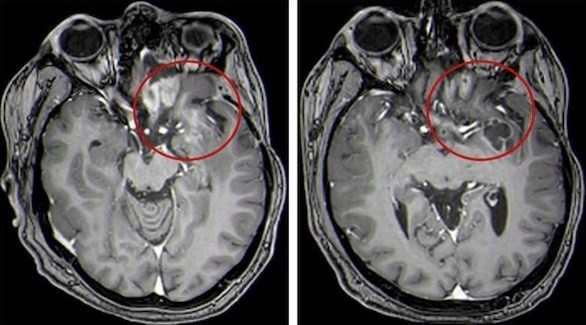

الرئيسية/طب وعلوم/علاج واعد لأورام الدماغ لدى الأطفال طب وعلوم علاج واعد لأورام الدماغ لدى الأطفال admin أرسل بريدا إلكترونيا 19/04/2021 4 أقل من دقيقة فيسبوك X لينكدإن Tumblr بينتيريست Reddit VKontakte Odnoklassniki Pocket تيلقرام admin أرسل بريدا إلكترونيا 19/04/2021 4 أقل من دقيقة فيسبوك X لينكدإن Tumblr بينتيريست Reddit VKontakte Odnoklassniki Pocket تيلقرام شاركها فيسبوك X لينكدإن Tumblr بينتيريست Reddit VKontakte Odnoklassniki Pocket تيلقرام مشاركة عبر البريد طباعة